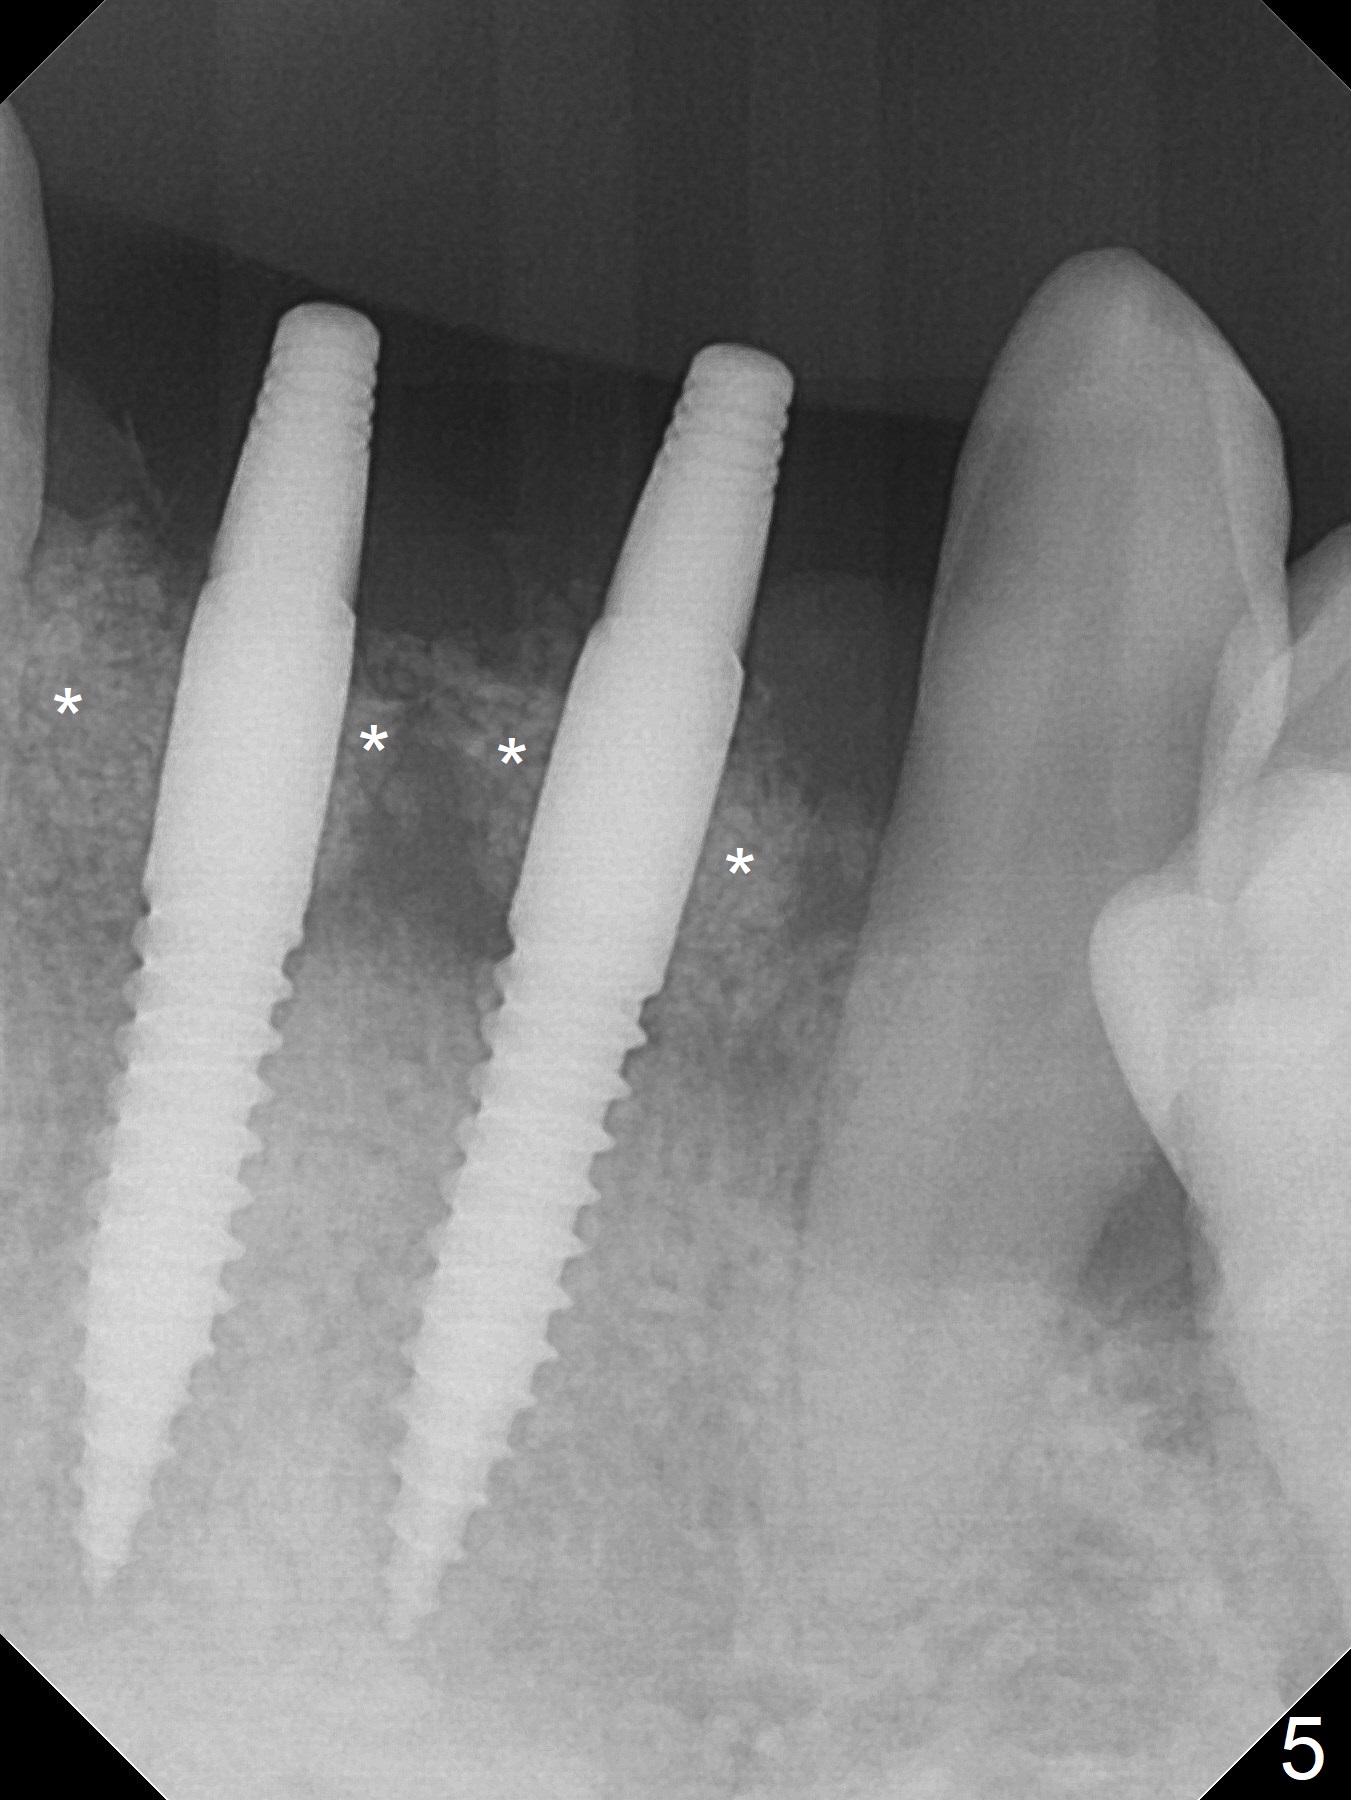

After extraction of 4 of the lower incisors, there are basically 2 sockets (#23/24 and 25/26), separated by the apparently midline bone (Fig.1 red line). In spite of using Lindamann bur to move the 25/26 osteotomy mesially, a 3x14(2) mm dummy implant remains close to the tooth #27 (Fig.2). The terminal branch of the Incisive Canal (<) is located between the lateral and central incisors. A de novo osteotomy (Fig.3 (1.5 mm drill)) is made mesial to the original one (O). While the 3x14(2) mm dummy implant is incompletely placed at #25/26, a 3x14(4) mm 1-piece one is placed at #23/24 (Fig.4). Finally the same implant is placed at #25/26 with placement of mineralized cortical/cancellous bone (Fig.5 *). When the large sockets are sutured, the supraerupted teeth #7-9 touch the lower gingiva (Fig.6). The incisal edge is reduced for clearance (Fig.7). Periodontal dressing is less likely to be dislodged with the incisal edge reduction (Fig.8,9). A provisional FPD is fabricated 1 week postop. Hard (Fig.10) and soft (Fig.11,12) tissues heal 5.5 months postop. The patient returns for crown cementation 3 months post impression (9 months postop, Fig.13,14).